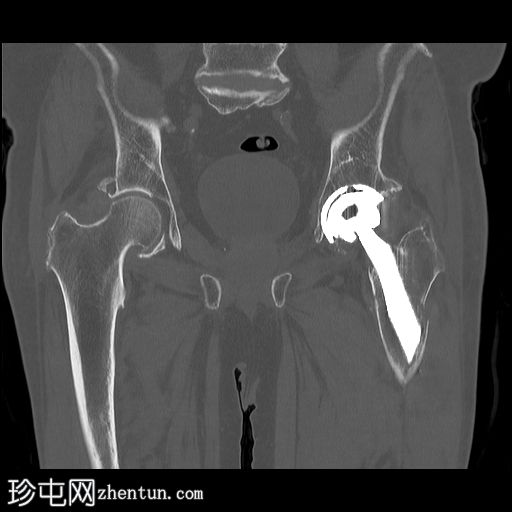

CT扫描

冠状骨窗

左股骨内存在轻微移位的假体周围骨折。

左大腿前部可见大量肌肉,可能提示血肿。但未见明显可引流积液。